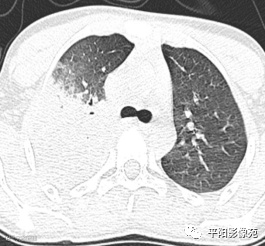

入院CT:

影像特征:X线片右肺中上野片状高密度影,下缘以叶间裂为界,上缘及外侧缘模糊;CT位于右肺上叶后段,呈片状实变影,内见支气管影,边缘模糊。

影像诊断:右肺上叶大叶性肺炎。